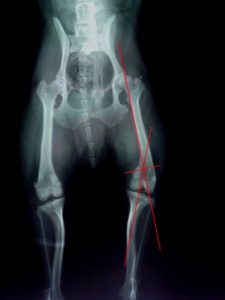

3、胫骨结节移位术

对胫骨嵴生长内旋者,将胫骨嵴移向外移动1~2公分,并用1~2枚克氏针固定。

4、截骨矫形术

如果病犬通过以上方法无效及同时膝关节严重畸形,应实施截骨矫形术,将股骨远端截断,纠正成角,使膝关节与髋关节和跗关节恢复成一条轴线上。

滑车再造成形术有时候会与胫骨结节移位术同步进行。个人认为,对于髌骨内翻,滑车沟过浅者,只要Q角在15°–20°度之间,仅需要加深滑车沟,同时在关节囊外做人造髌内侧韧带就可以了。术后的恢复也应该是比较理想的。